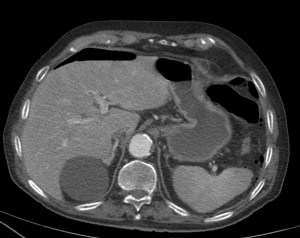

Paciente con diarrea y vómitos y dolor abdominal intenso. Antecedentes de fibrilación auricular. Analítica con discreta leucocitosis.

Se sospecha Isquemia intestinal. Veamos las pruebas complementarias de imagen:

En conclusión, estamos ante un cuadro de posible isquemia intestinal perforada, de ahí el neumoperitoneo.